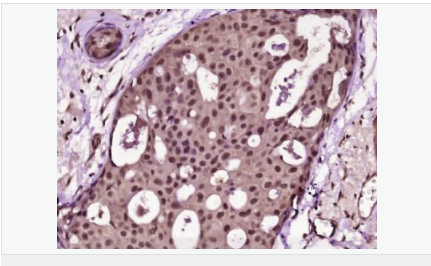

| 產(chǎn)品應(yīng)用 | ELISA=1:5000-10000 IHC-P=1:100-500 IHC-F=1:100-500 Flow-Cyt=1μg/Test (石蠟切片需做抗原修復(fù)) not yet tested in other applications. optimal dilutions/concentrations should be determined by the end user. |

| 產(chǎn)品介紹 | Proliferation Marker Ki67 antigen is the prototypic cell cycle related nuclear protein, expressed by proliferating cells in all phases of the active cell cycle (G1, S, G2 and M phase). It is absent in resting (G0) cells. Ki67 antibodies are useful in establishing the cell growing fraction in neoplasms (immunohistochemically quantified by determining the number of Ki67 positive cells among the total number of resting cells = Ki67 index). In neoplastic tissues the prognostic value is comparable to the tritiated thymidine labelling index. The correlation between low Ki67 index and histologically low grade tumours is strong. Ki67 is routinely used as a neuronal marker of cell cycling and proliferation. Function: Thought to be required for maintaining cell proliferation. Subcellular Location: Nucleus. Chromosome. Predominantly localized in the G1 phase in the perinucleolar region, in the later phases it is also detected throughout the nuclear interior, being predominantly localized in the nuclear matrix. In mitosis, it is present on all chromosomes. Similarity: Contains 1 FHA domain. SWISS: P46013 Gene ID: 4288 Database links: Entrez Gene: 4288 Human Entrez Gene: 17345 Mouse Omim: 176741 Human SwissProt: P46013 Human SwissProt: Q91VE6 Mouse Unigene: 689823 Human Unigene: 80976 Human Unigene: 4078 Mouse Unigene: 233802 Rat Important Note: This product as supplied is intended for research use only, not for use in human, therapeutic or diagnostic applications. 細胞增殖標志物(Proliferation Marker) Ki67與PCNA一樣,為細胞增殖的一種標記,在細胞凋亡中S、G2 、M期均有表達,G0期缺如。 Ki-67增殖指數(shù)高低與許多腫瘤的分化程度、浸潤、轉(zhuǎn)移以及預(yù)后密切相關(guān),因此被廣泛作為各種惡性腫瘤的必檢項目之一。 |